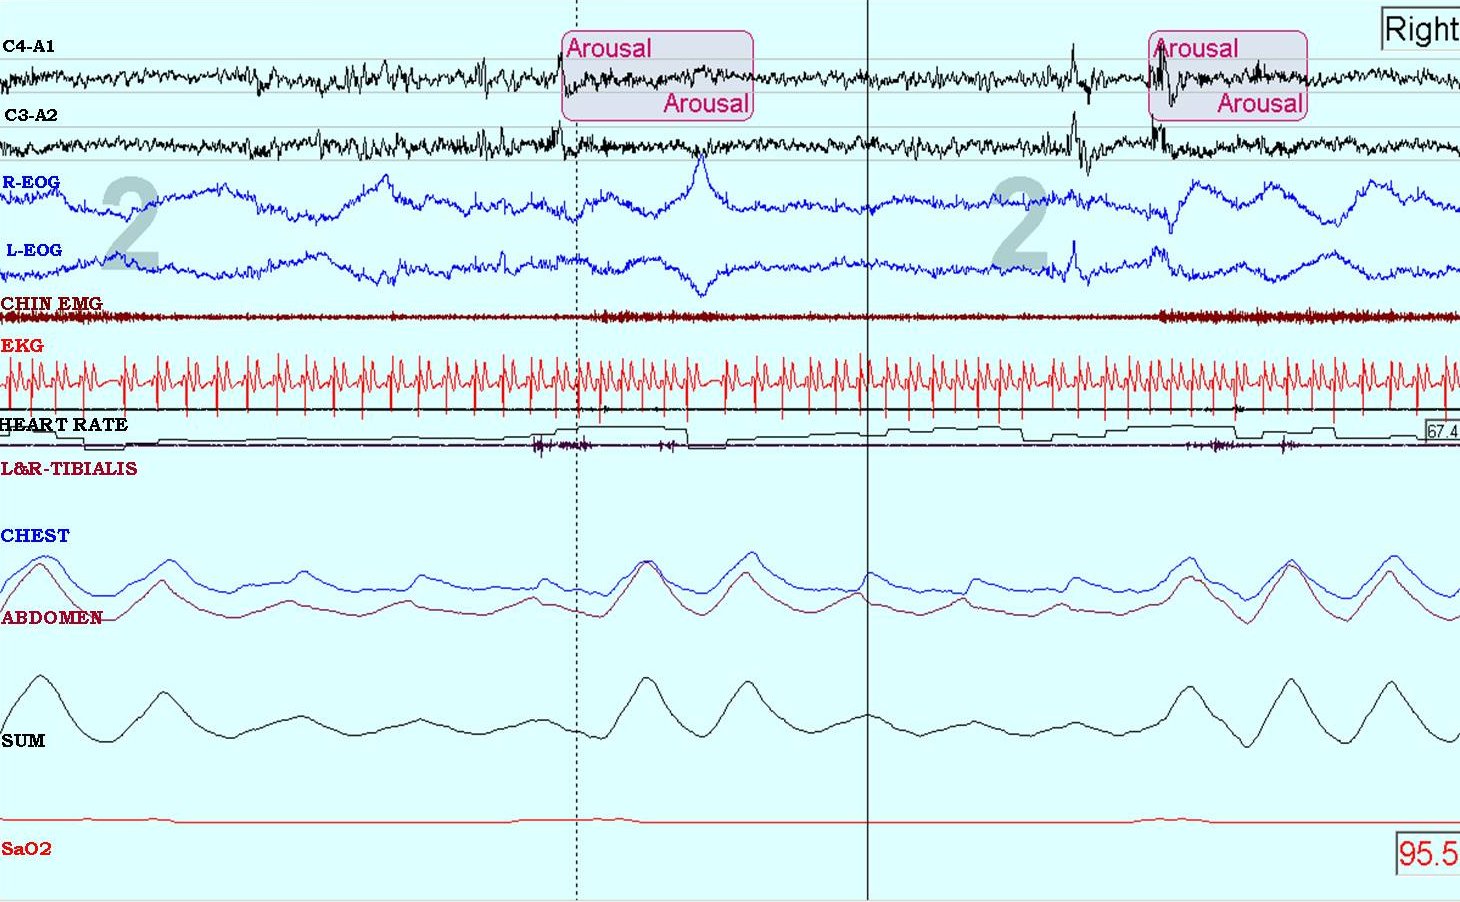

A diagnostic sleep study showed a mild obstructive sleep apnea with an overall apnea-hypopnea index (AHI) of 14.4 events/hr and mild periodic limb movements during sleep with an index of 14.1 events/hr. Interestingly, when he was in the right lateral position, his AHI was 87 events/hr compared to only 17 events/hr on the left side and 6 events/hr while supine. He spent 22 minutes on his right side all of which was spent in stages N1 and N2 sleep. The figure below shows an epoch from the polysomnogram (PSG) recording demonstrating 2 obstructive hypopneas as indicated by the out-of-phase chest and abdominal movements on respiratory inductance plethysmography, accompanied by arousals from sleep while in the right lateral position.